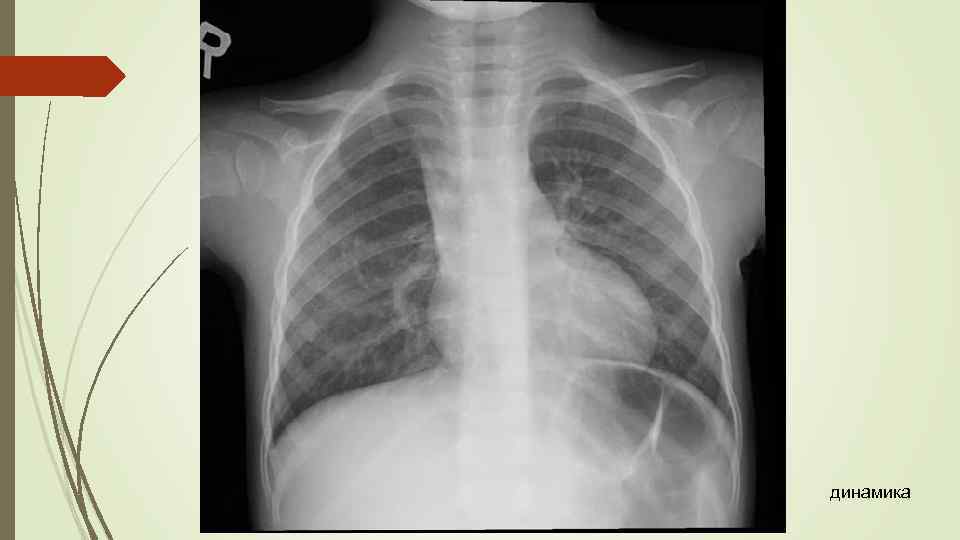

динамика

динамика

Бронхопневмония Характерно наличие двухсторонних множественных очаговых теней. Контуры очагов нечеткие, интенсивность тени небольшая. Инфильтрация неоднородна. Мелкие, малоинтенсивные очаги не всегда выявляются на снимках. Легочный рисунок усилен на всем протяжении легких. Корни расширены, не структурны. Как правило, отмечается реакция плевры, могут быть и экссудативные плевриты.

Бронхопневмония Характерно наличие двухсторонних множественных очаговых теней. Контуры очагов нечеткие, интенсивность тени небольшая. Инфильтрация неоднородна. Мелкие, малоинтенсивные очаги не всегда выявляются на снимках. Легочный рисунок усилен на всем протяжении легких. Корни расширены, не структурны. Как правило, отмечается реакция плевры, могут быть и экссудативные плевриты.